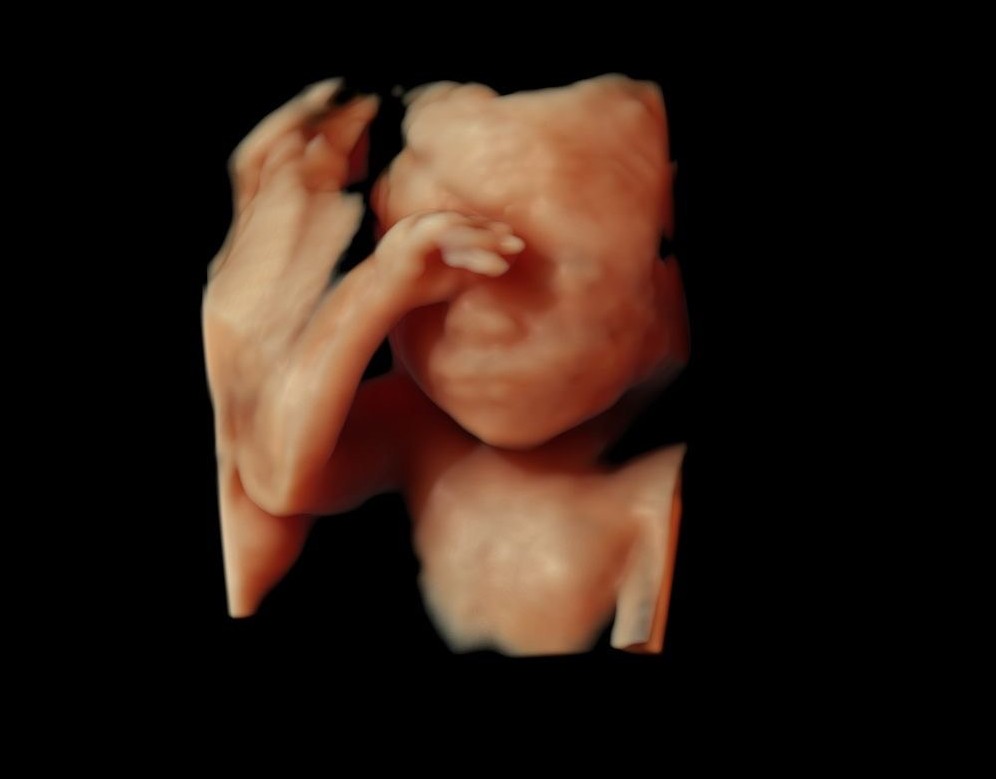

Kaelalülid on selgelt nähtavad. 23. nädalal kaalub loode umbes 550 grammi. 23. nädalast on hea visualiseerida 4D ultraheliuuringu käigus loote näojooni.

24. nädalal on loode umbes 30 sentimeetri pikkune ja kaalub umbes 650 grammi.

- Soovi korral 4D ultraheliuuring (24.–32. nädal)

Loote kaal on umbes 1 kilogramm ja ta on 35 sentimeetri pikkune. See on parim aeg 4D ultraheliuuringu käigus loote näo vaatamiseks.

See on aeg, mil võiks hakata tasapisi mõtlema sünnituse peale ja uurida, keda sooviks naine sünnitusele tugiisikuks. Sel ajal on võimalik koos käia ka 4D ultraheliuuringul, mis annab infot lapse tervise ja arengu kohta ning võimaldab tulevastel lapsevanematel jälgida reaalajas oma lapse tegevust, tekitades elevust ja pakkudes positiivseid emotsioone.